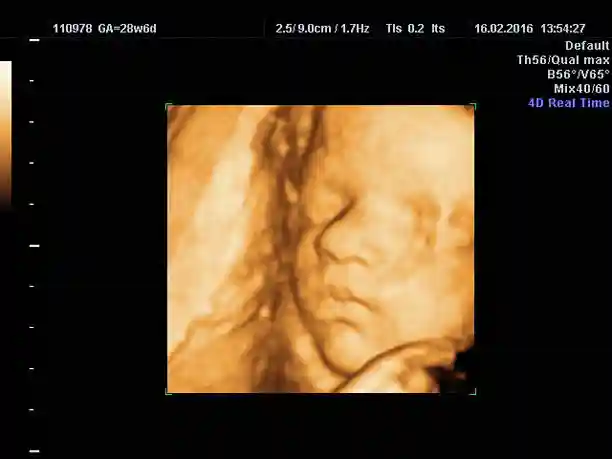

이유는, 미리 예약해둔 뱃속 태아 3D 촬영을 3회 예약해뒀는데, 그게 32주까지 찍는 거라서 그렇습니다.